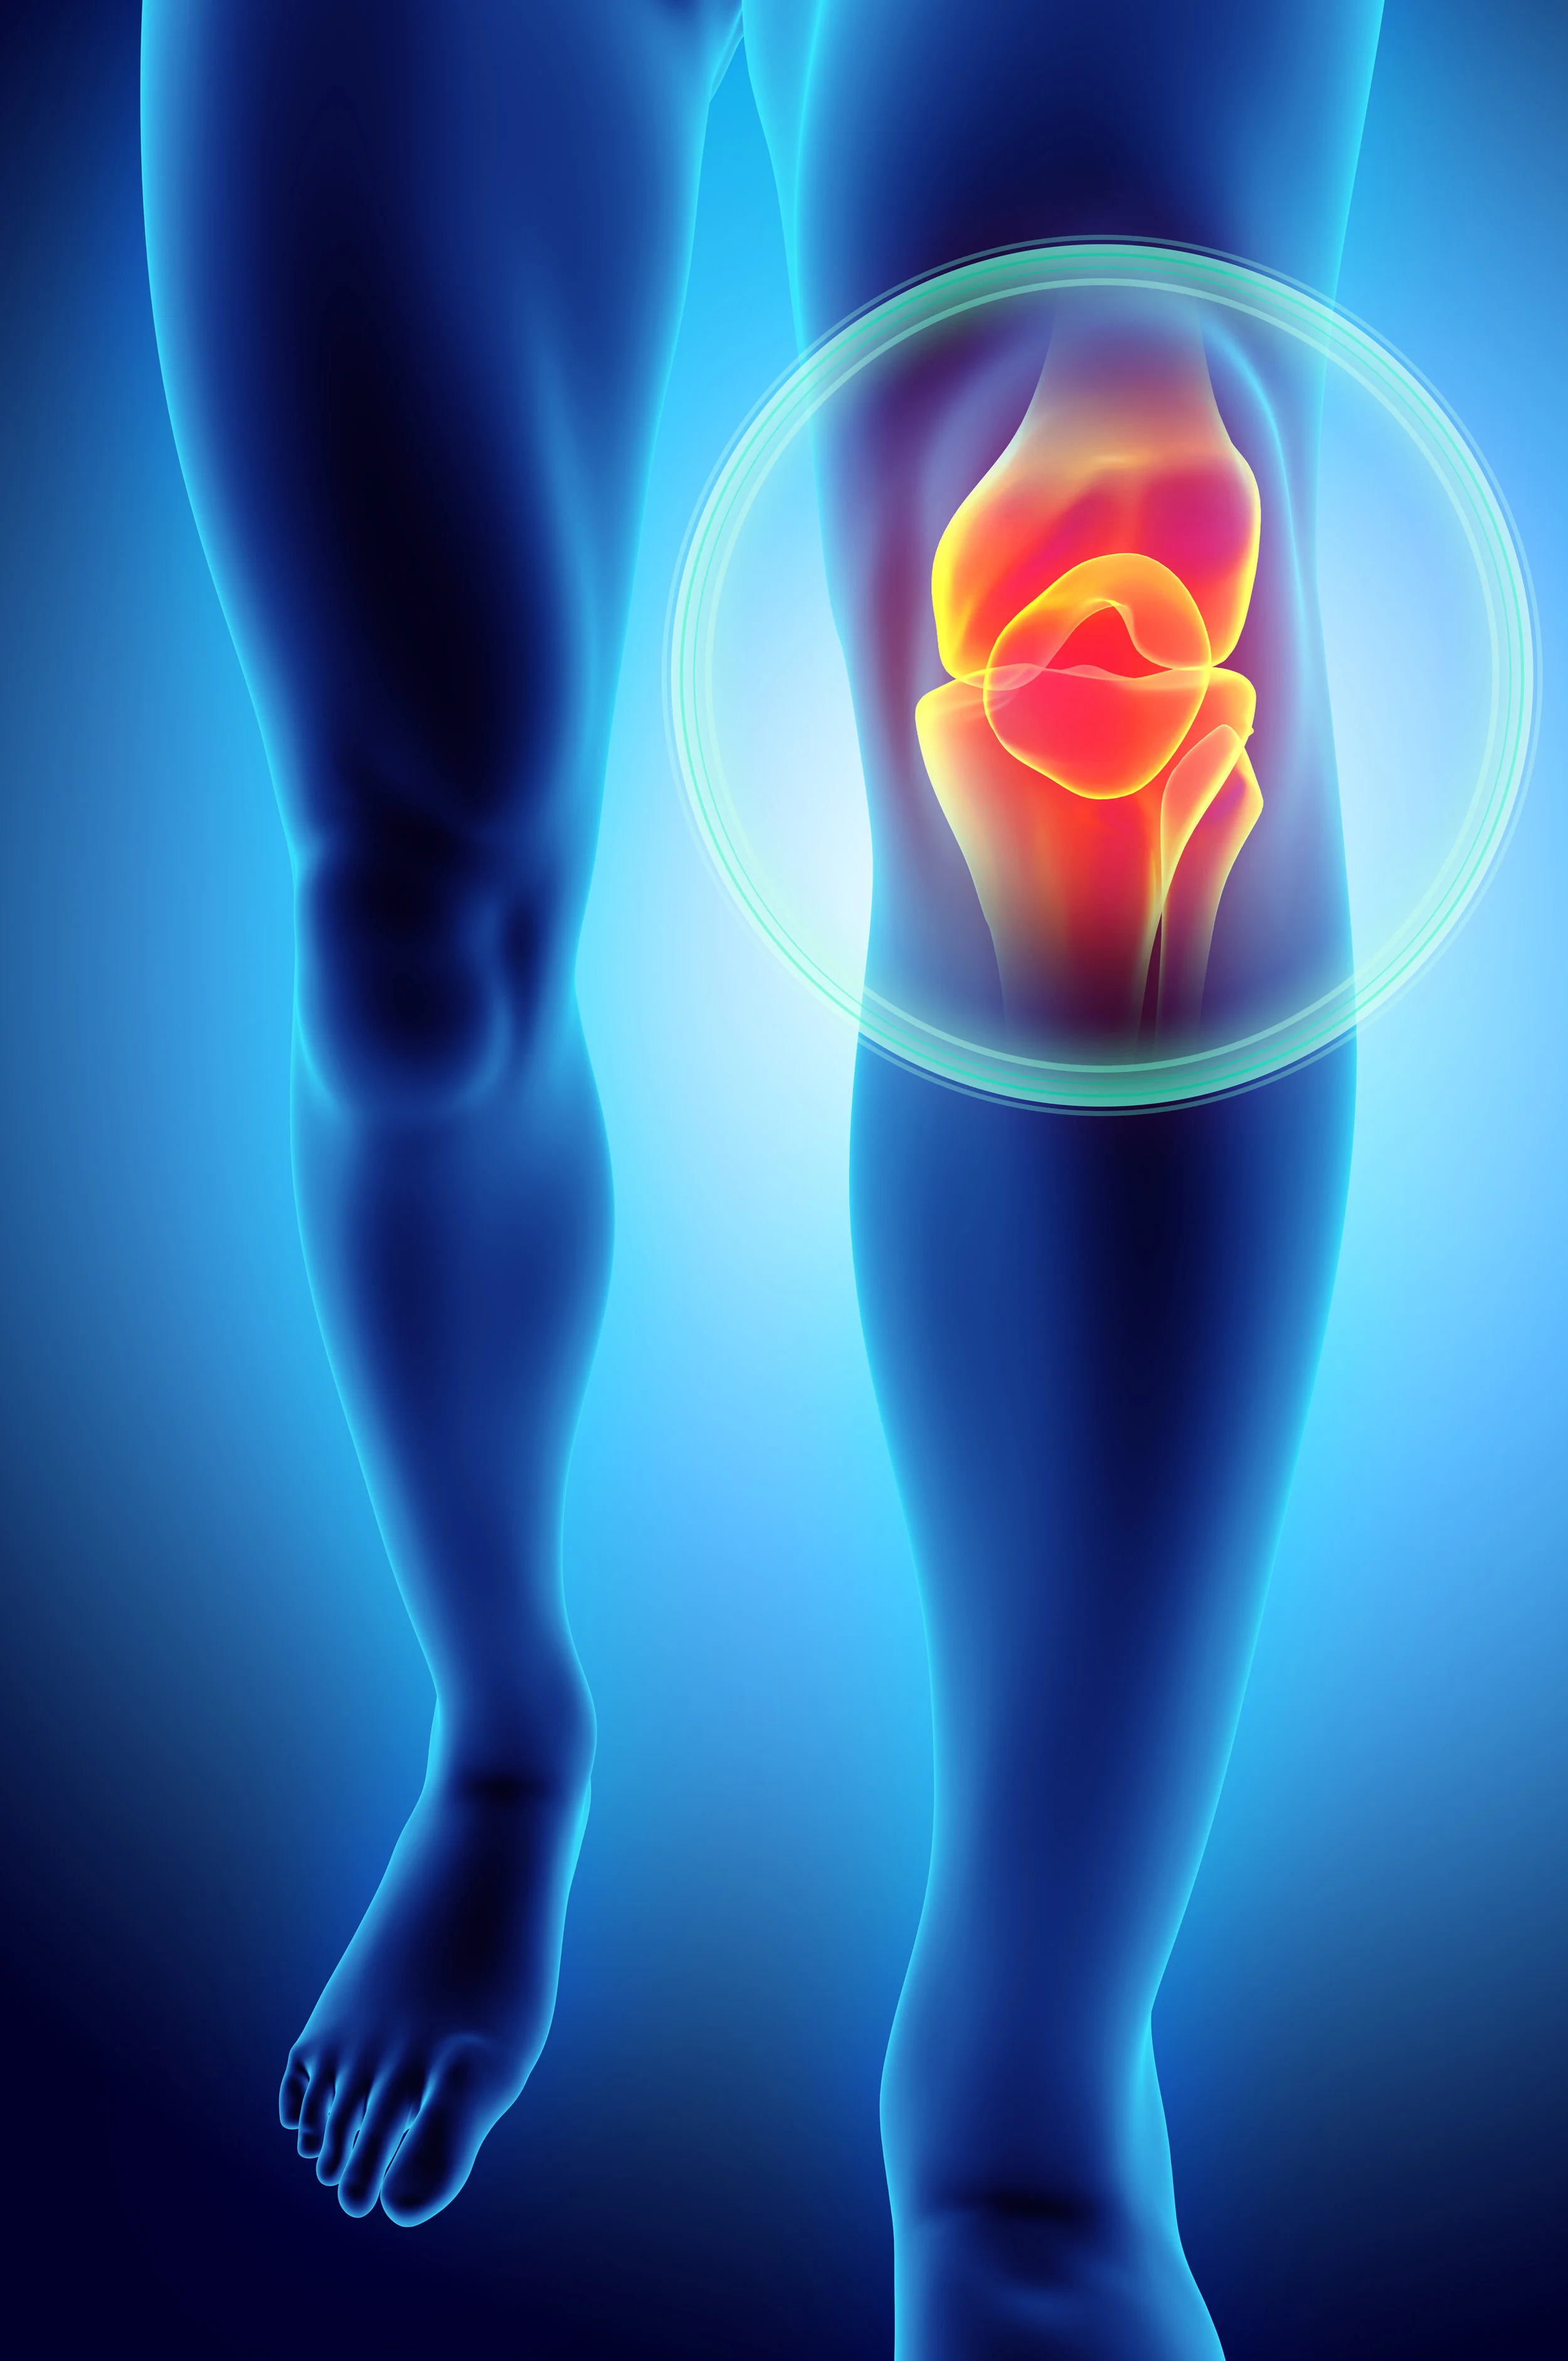

Meniscus Tears

Dr. Raynor gives an explanation of the different types of meniscus tears and the treatment options available.